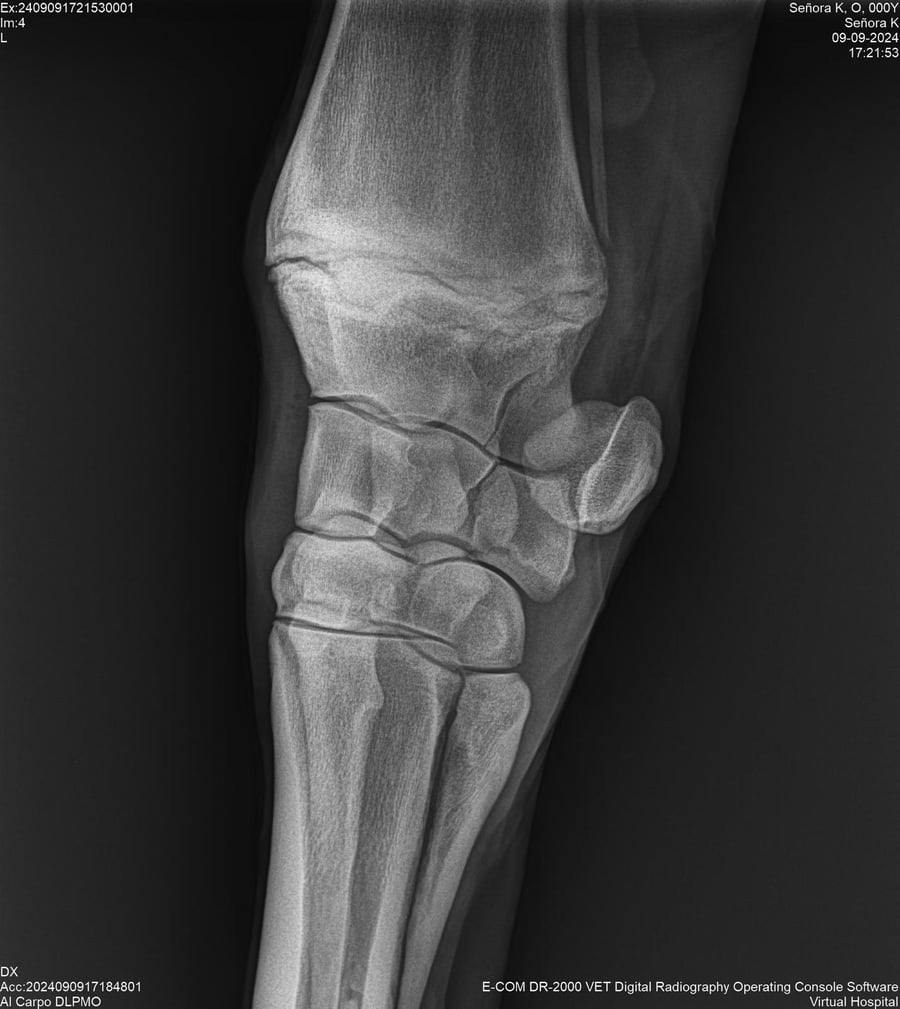

LOTE 44, SEÑORA K

Identificador: #291147-

Generacion 2022